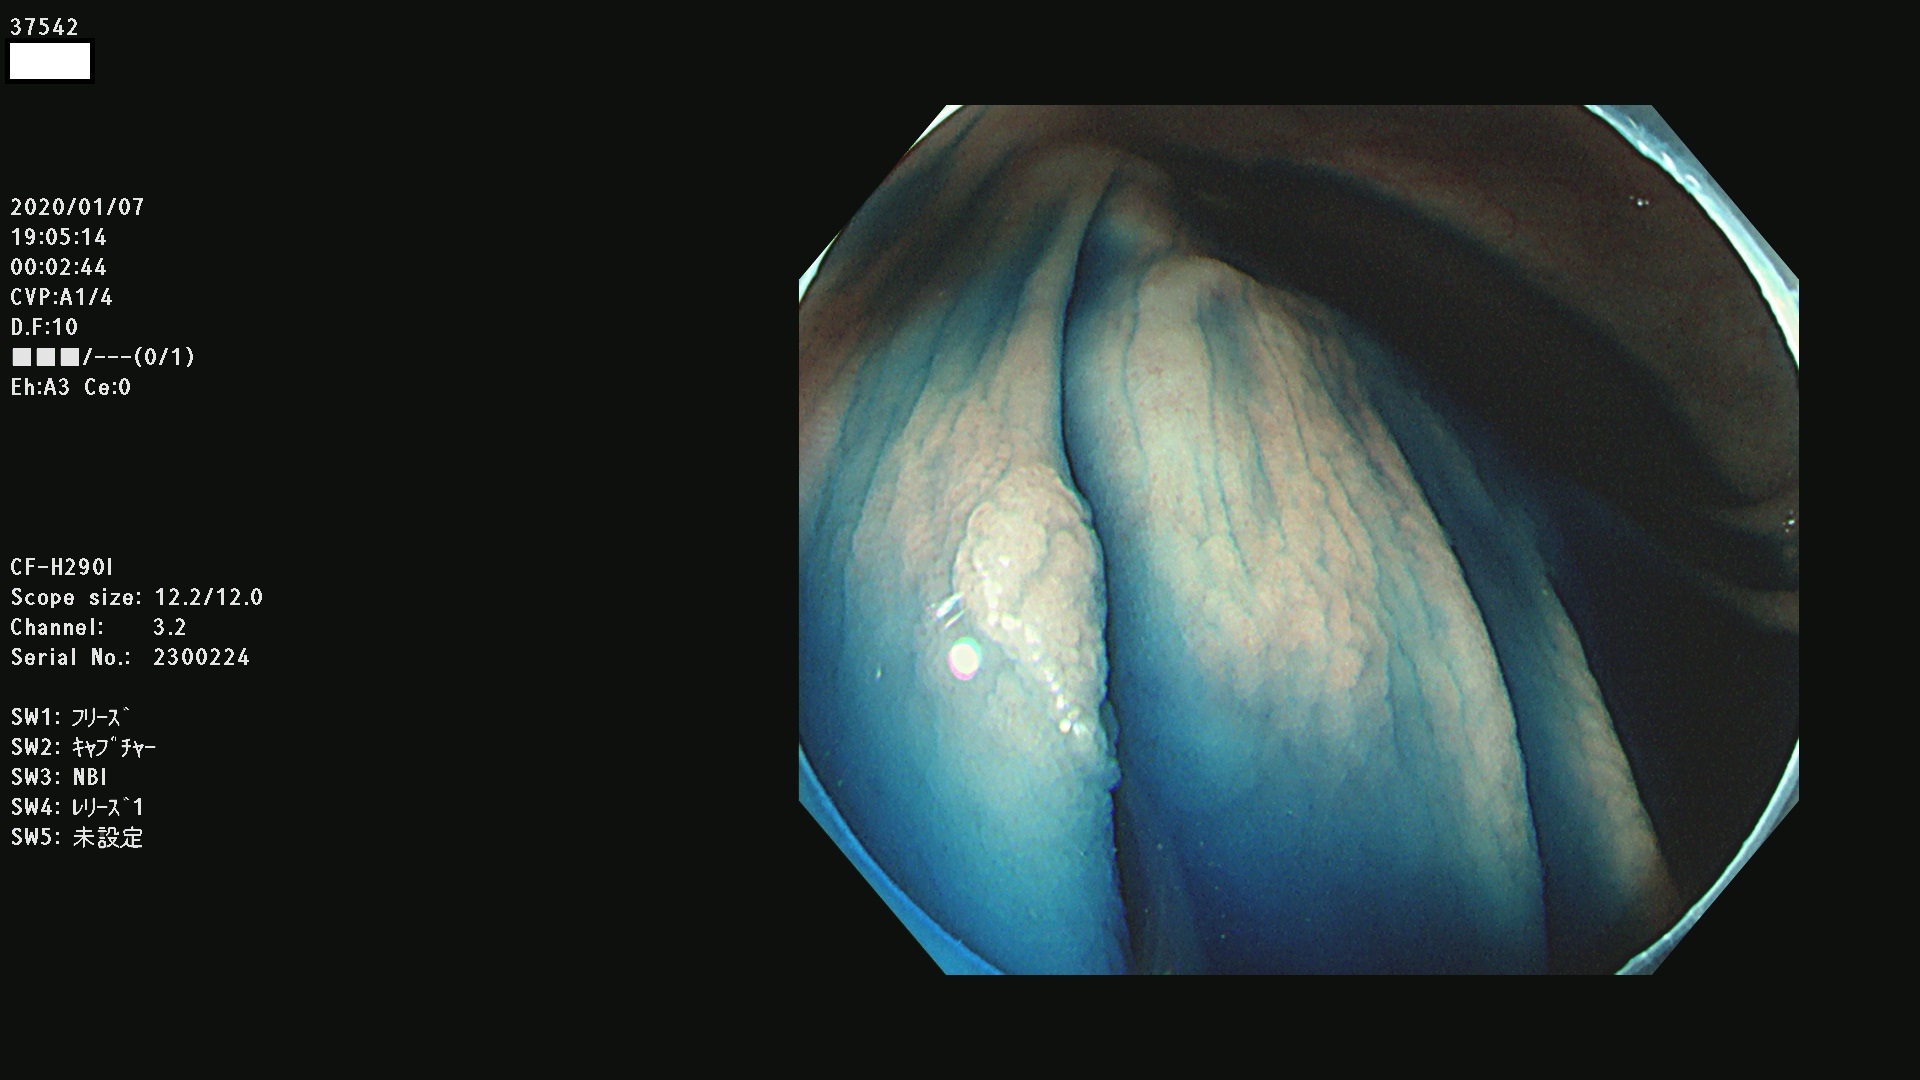

発見困難で危険性の高い平坦型病変(上記100名より抽出) ![]()